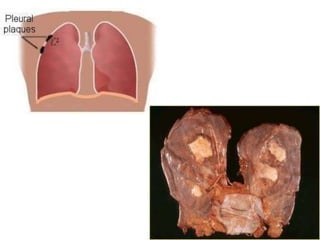

Pleural Disease Associated with

Asbestosis

 Pleural Plaques

 Pleural Thickening

 Pleural Effusion

 Mesothelioma

Pleural Plaques

 Smooth white raised lesions located on the posterolateral

aspect of the parietal pleura or diaphragm

 Plaques vary in size & shape

 Asymptomatic in pts without parenchymal disease

 Presence of plaques is associated with likelihood of

developing parenchymal disease

 Rarely seen before 20yrs after exposure

Pleural Disease Associatedwith Asbestosis  Pleural Plaques  Pleural Thickening  Pleural Effusion  Mesothelioma

Pleural Plaques  Smoothwhite raised lesions located on the posterolateral aspect of the parietal pleura or diaphragm  Plaques vary in size & shape  Asymptomatic in pts without parenchymal disease  Presence of plaques is associated with likelihood of developing parenchymal disease  Rarely seen before 20yrs after exposure